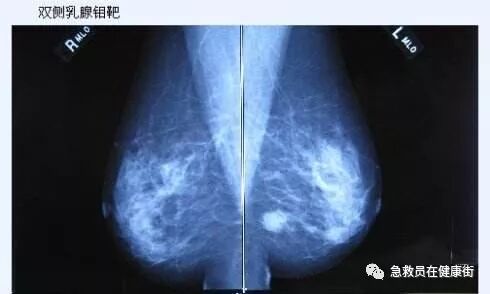

3影像引导下粗针活检适应症

1. 影像学检查发现的可疑病灶。

2. 钼靶片可见的局灶或可疑微小簇状钙化。

3. 对于重度增生性病变,可以达到诊断目的。

4. 钼靶片乳腺结构扭曲,超声可见,鉴别病变性质。

5.乳腺恶性肿瘤的术前诊断。

6. 新辅助化疗或内分泌治疗前(局部晚期乳腺癌)的诊断和治疗后的疗效判定。

7. 了解乳腺癌保乳术术前乳腺其他部位多发病灶的性质。

8. 了解乳腺癌保乳术术后切口周围和其他象限新生病灶的性质。